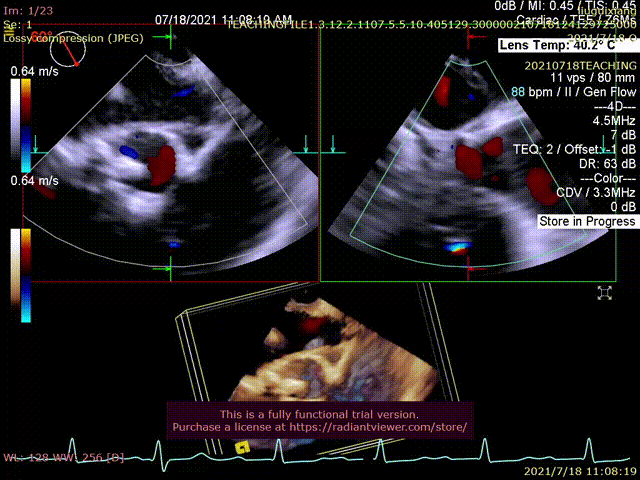

患者为79岁老年女性,一周前出现无诱因胸闷不适,咳喘明显,由当地医院转至鼓楼医院急诊。超声心动图显示左房内径增大,左室心肌增厚,EF值50%,主动脉瓣峰值流速5.68m/s,峰值压差128mmHg,主动脉瓣瓣膜增厚、粘连、钙化,提示主动脉瓣重度狭窄伴轻度关闭不全。二尖瓣中度关闭不全,三尖瓣轻-中度关闭不全伴轻度肺动脉高压,少量心包积液。

术中三维超声测量距离及左冠血流

冠脉开口高度稍低,左冠瓣瓣叶偏长,综合瓦氏窦内径等因素考虑,有一定冠脉遮挡风险,术中可借助食道超声测量钙化到左冠开口的距离以及评估冠脉血流,再决定是否行冠脉保护。

超声提示形态及血流动力学欠佳

超声评估,形态及血流动力学良好